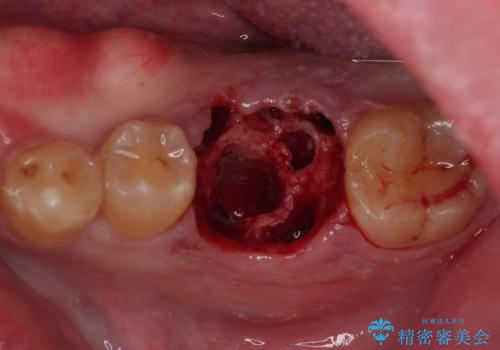

歯槽骨の状態は良好であったため、抜歯即時埋入インプラントによる補綴治療を行うこととしました。

インプラント埋入時に植立具合の安定性を測定したところ、十分な数値が得られたため、速やかに仮歯を装着して咬合回復をさせることができました。

抜歯を含めた外科処置を1回に抑えることができ、あっという間に治療を終えることができました。